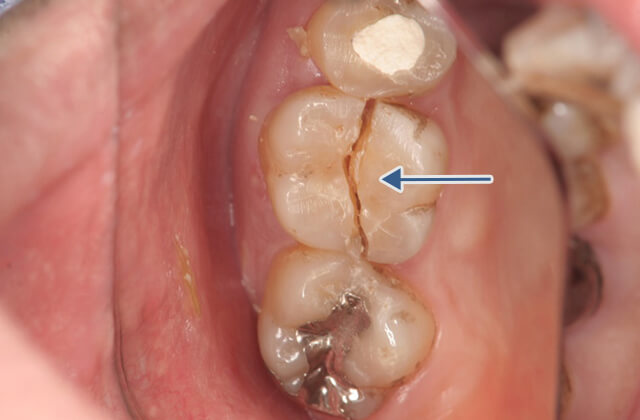

左記の症例のように歯が破折してしまう←ことがあります。これは、以前に歯医者さんで神経を抜いていた歯(無髄歯)に多く見られます。破折・亀裂が生じた歯は抜歯と判断されがちですが保存できる場合も多くあります。そのためには必要な検査を受け詳細な現状分析を行い正確な診断から最良の治療方法を選び確実にその治療を専門医が実践していくことで歯の寿命を長くできます。

歯肉剥離掻把治療を行い歯根が破折(矢印部分にヒビが入り割れている)している事を確認して破折線の接着による治療を行いました